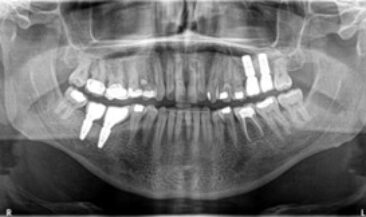

Sinus lift & block graft reconstruction